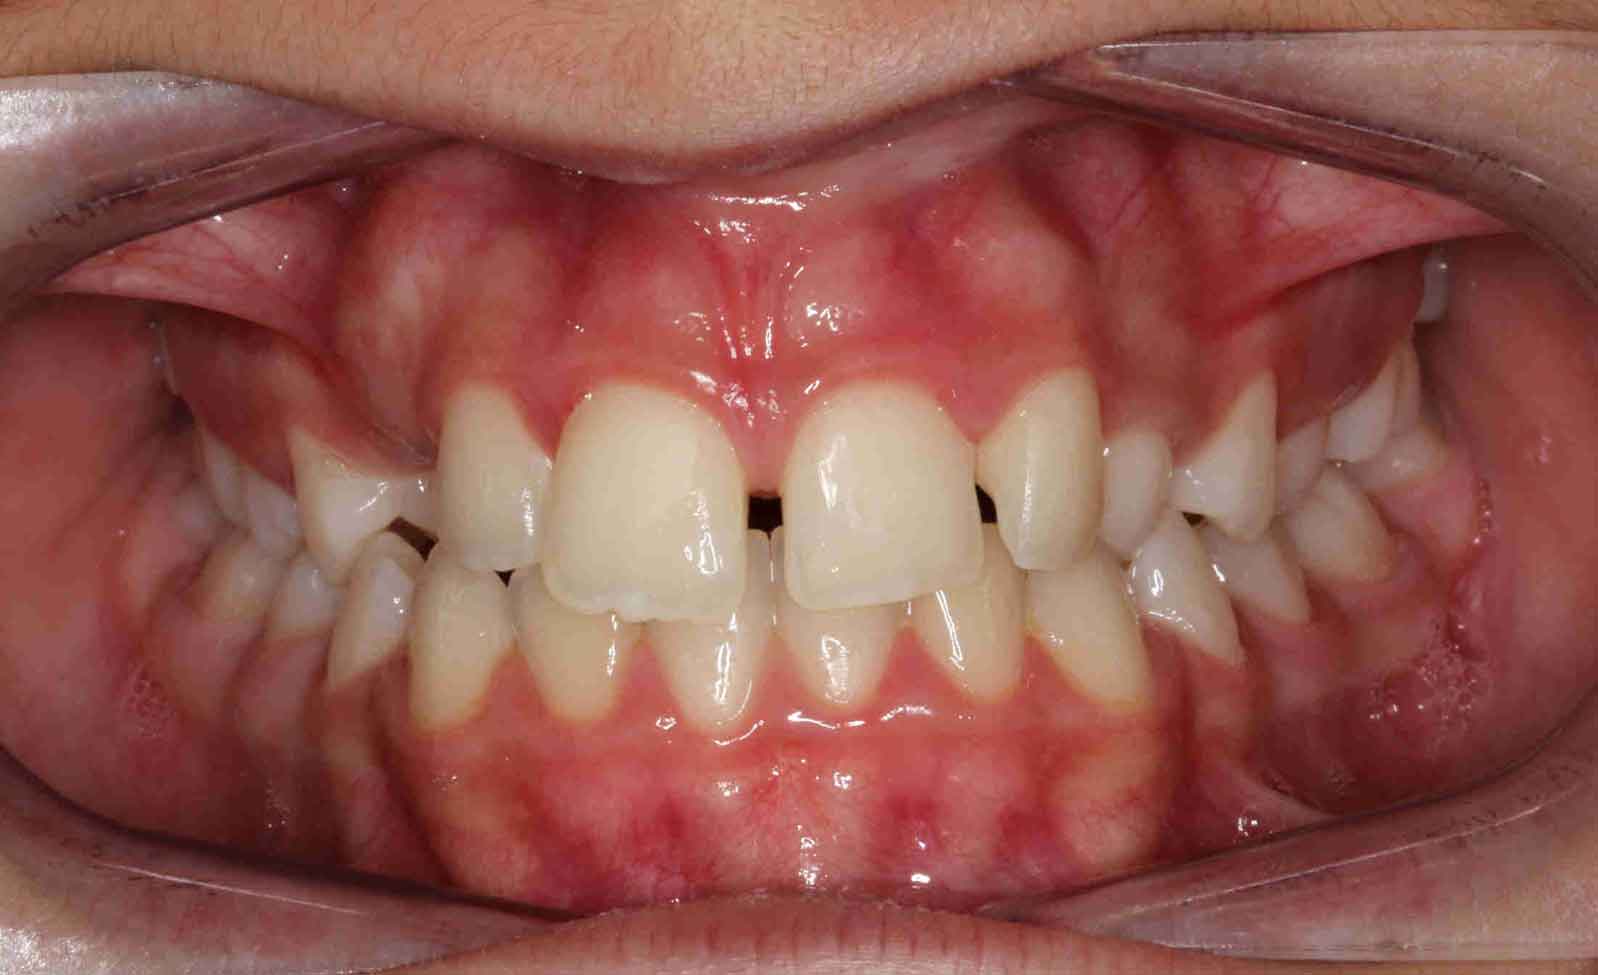

Caninos Impactados

En las siguientes imágenes puedes ver distintos resultados del tratamiento, deslizando la barra central de un lado a otro.